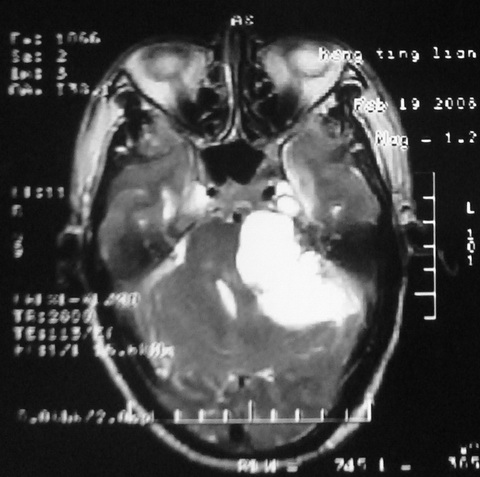

m,72,头疼,头晕两年,伴视力模糊三月,饮食呛咳两天。pe:颈部抵抗,左眼突出,左眼瞳孔约3mm,对光反射消失,双眼失明,伸舌困难,双肺呼吸音粗,心率110次/分,左上肢肌力i级,左下肢屈曲,肌张力高。现有08年2月19mri平扫及10年2月8日mri增强请会诊。ct病灶呈低密度伴散在点、片状等密度区,无明确钙化(无ct片资料可供上传)。[

脑外肿瘤,囊实性,环状不规则强化,内听道扩大,考虑神经源性肿瘤

左侧桥小脑区占位伴梗阻性脑积水----考虑 1神经鞘瘤 2室管膜瘤。

左侧桥小脑区神经鞘瘤伴梗阻性脑积水。

听神经瘤

脑外肿瘤,病灶呈匍匐蔓延,表皮样囊肿可能性大。

脑外肿瘤,病灶呈匍匐蔓延,表皮样囊肿可能性大。支持!

左侧桥脑小脑角区肿瘤并脑积水,考虑听神经瘤,脑膜瘤?

考虑听神经瘤

左侧桥脑小脑角区肿瘤并脑积水,考虑听神经瘤,